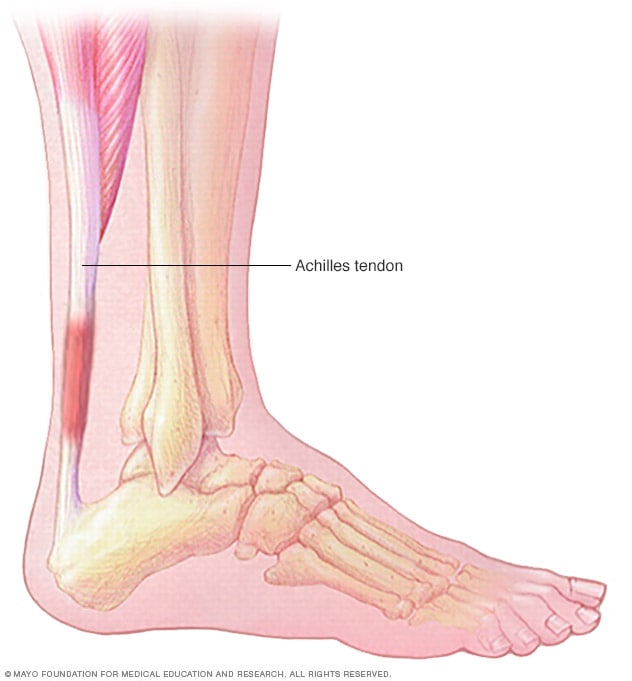

pictures of achilles tendon

Achilles tendinitis – Mayo Clinic